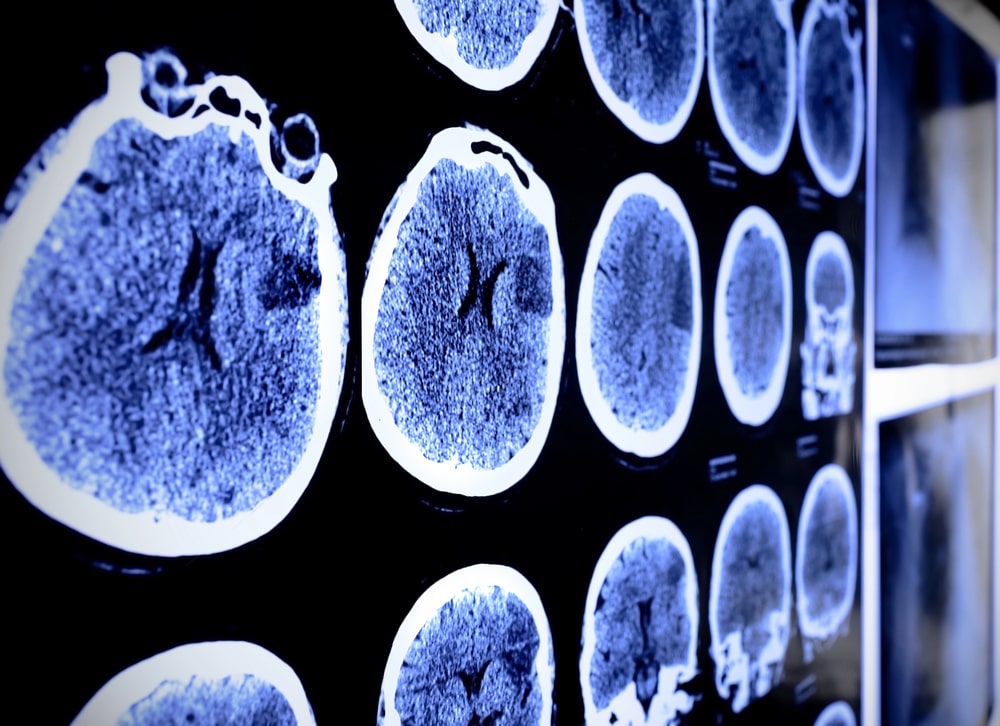

A traumatic brain injury (TBI) is one of the most life-altering injuries a person can suffer. The brain is responsible for all cognitive functions as well as many motor functions. Even when a person survives a TBI, it can change their life completely. A person with a TBI may also require lifelong care. If you or a loved one is suffering from a TBI from another person’s negligence or recklessness, call our team today to work with our Brooklyn, NY TBI lawyer!

TBIs can range in severity, from mild concussions to injuries that can result in permanent cognitive, emotional, and physical impairment. Even TBI injuries considered “mild” can have untold effects on a person’s life. Besides needing money for immediate medical care, individuals may need permanent disability. An injury can also mean a person is unable to work, leading to lost wages. In these situations, a TBI can especially be a financial hurdle for the victim’s family.

Many accidents can cause a TBI, including car accidents, construction accidents, and slips and falls. In rare cases, even medical malpractice can result in a TBI. Regardless of the cause, a victim or their family has every right to pursue compensation. Our team understands how to prove the full extent of a brain injury, working with medical experts, neurologists, and life care planners to build a case that reflects the reality of your condition.